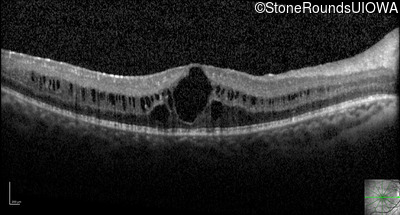

Optical Coherence Tomography - Left - 20/20 -2

Exemplar / OCT Stack